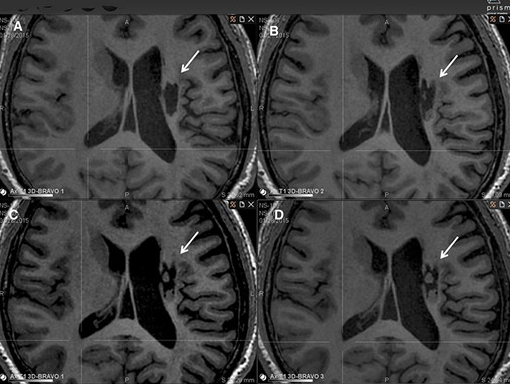

神經(jīng)干細(xì)胞移植治療24個月后,患者運動能力和日常生活能力改善,神經(jīng)受損程度持續(xù)降低并且影像學(xué)也持續(xù)改善。

影像學(xué)檢查:在 6 個月的隨訪中,所有 9 名受試者均觀察到新組織,源自腦軟化梗塞腔。該腔內(nèi)組織外觀具有以下特征:短期活力(術(shù)后第一次 MRI 與基線相比的組織外觀)—9 例中有 9 例;生長(術(shù)后至少兩次 MRI 中新組織增加)—6 例中有 6 例;穩(wěn)定(術(shù)后至少兩次 MRI 中新組織沒有變化;即生長平臺期,最長為 24 個月)—6 例中有 5 例;無法獲得 24 個月后的長期活力。

(A)基線時,(B) 6 個月隨訪時,(C) 12 個月隨訪時,(D) 24 個月隨訪時。